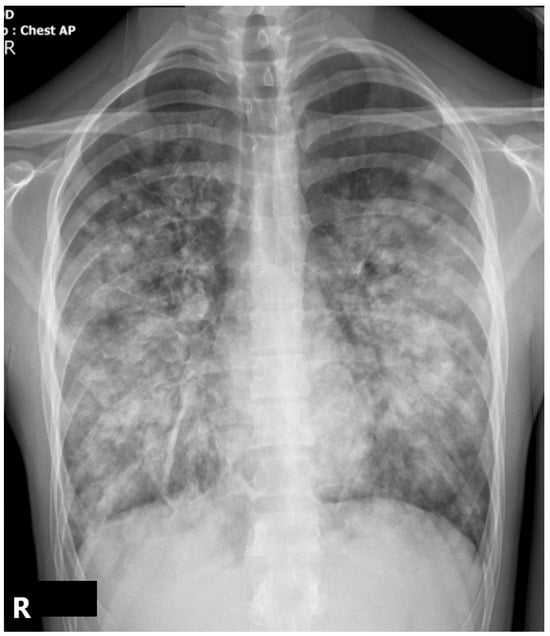

2.3. Case Evolution